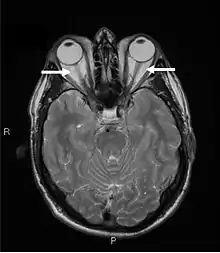

Magnetic resonance imaging of the orbits, showing congestion of the retro-orbital space and enlargement of the extraocular muscles (arrows), consistent with the diagnosis of Graves' ophthalmopathy.

Orbital imaging is an interesting tool for the diagnosis of Graves' ophthalmopathy and is useful in monitoring patients for progression of the disease. It is, however, not warranted when the diagnosis can be established clinically. Ultrasonography may detect early Graves' orbitopathy in patients without clinical orbital findings. It is less reliable than the CT scan and magnetic resonance imaging (MRI), however, to assess the extraocular muscle involvement at the orbital apex, which may lead to blindness. Thus, CT scan or MRI is necessary when optic nerve involvement is suspected. On neuroimaging, the most characteristic findings are thick extraocular muscles with tendon sparing, usually bilateral, and proptosis.